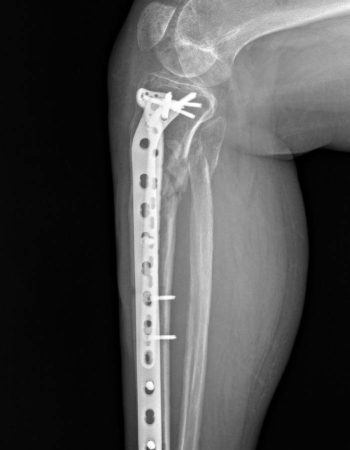

Післяопераційний період проходив без ускладнень і на 10 день після поступлення було проведено наступне етапне оперативне втручання: відкрита репозиція, металоостеосинтез пластинами.

Пацієнтка якісно провела реабілітацію і вже зараз починає навантажувати травмовану кінцівку, щоб згодом повернутися на роботу!